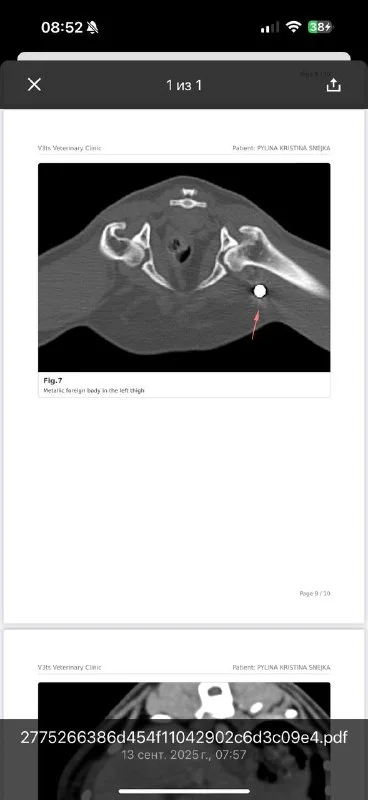

Новости от кошки Снежки :)

В заключении написано: «На этом этапе правильнее: Сделать ТАБ лимфоузлов (биопсия) - у Снежки взяли образец и отправили сразу, одновременно с кт - там все чисто 😍😍😍

Еще - у Снежки в бедре дробинка 😭😭😭 такие находки пугают не меньше метастаз …

Еще - хронический отит 💔

Из-за увеличенных лимфатических узлов (я надеюсь они увеличены из-за отита)

и мелких узлов в легких - коте нужен рентген через пару месяцев..

Необходимо контролировать состояние, тк карцинома - это агрессивный вид рака :(

Будем лечить ушки, в остальном - оставляю в покое эту рысьно-манульную мордочку в покое на пару месяцев..)☺️